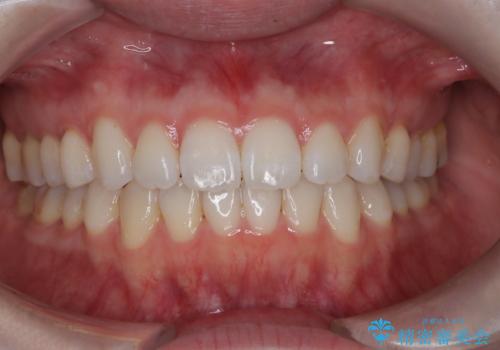

- 上下の前歯の凸凹が気になり、来院されました。

インビザラインで綺麗に仕上がり、満足していただきました。